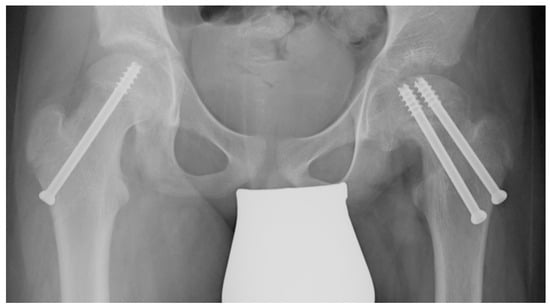

When the resection of the hinge is completed, the osteotomy is closed, reducing the head over the neck using a reducing maneuver. To check the correct alignment, a C-arm intensifier is used. Since the osteotomy slightly shortens the proximal femur, the reduction maneuver does not stretch the retinacular vessels. Making a lateral incision, under a fluoroscopic guide, two cannulated screws are used to fix the osteotomy. The joint capsule is carefully closed, and then the wounds are closed in layers. Prophylactic stabilization of the contralateral hip is usually performed using a single cannulated screw to reduce the risk of metachronous slippage (Figure 2) [].

Figure 2.

A patient treated in the left hip using VASSCO and stabilized with two screws. On the right, a single cannulated screw is placed to reduce the risk of metachronous slippage.